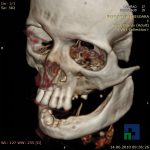

- Diagnosticul fracturilor:

- Complexe cranio-sinusale

- Complexe cranio-etmoidale

- Complexe cranio-orbitare

- Complexe cranio-faciale